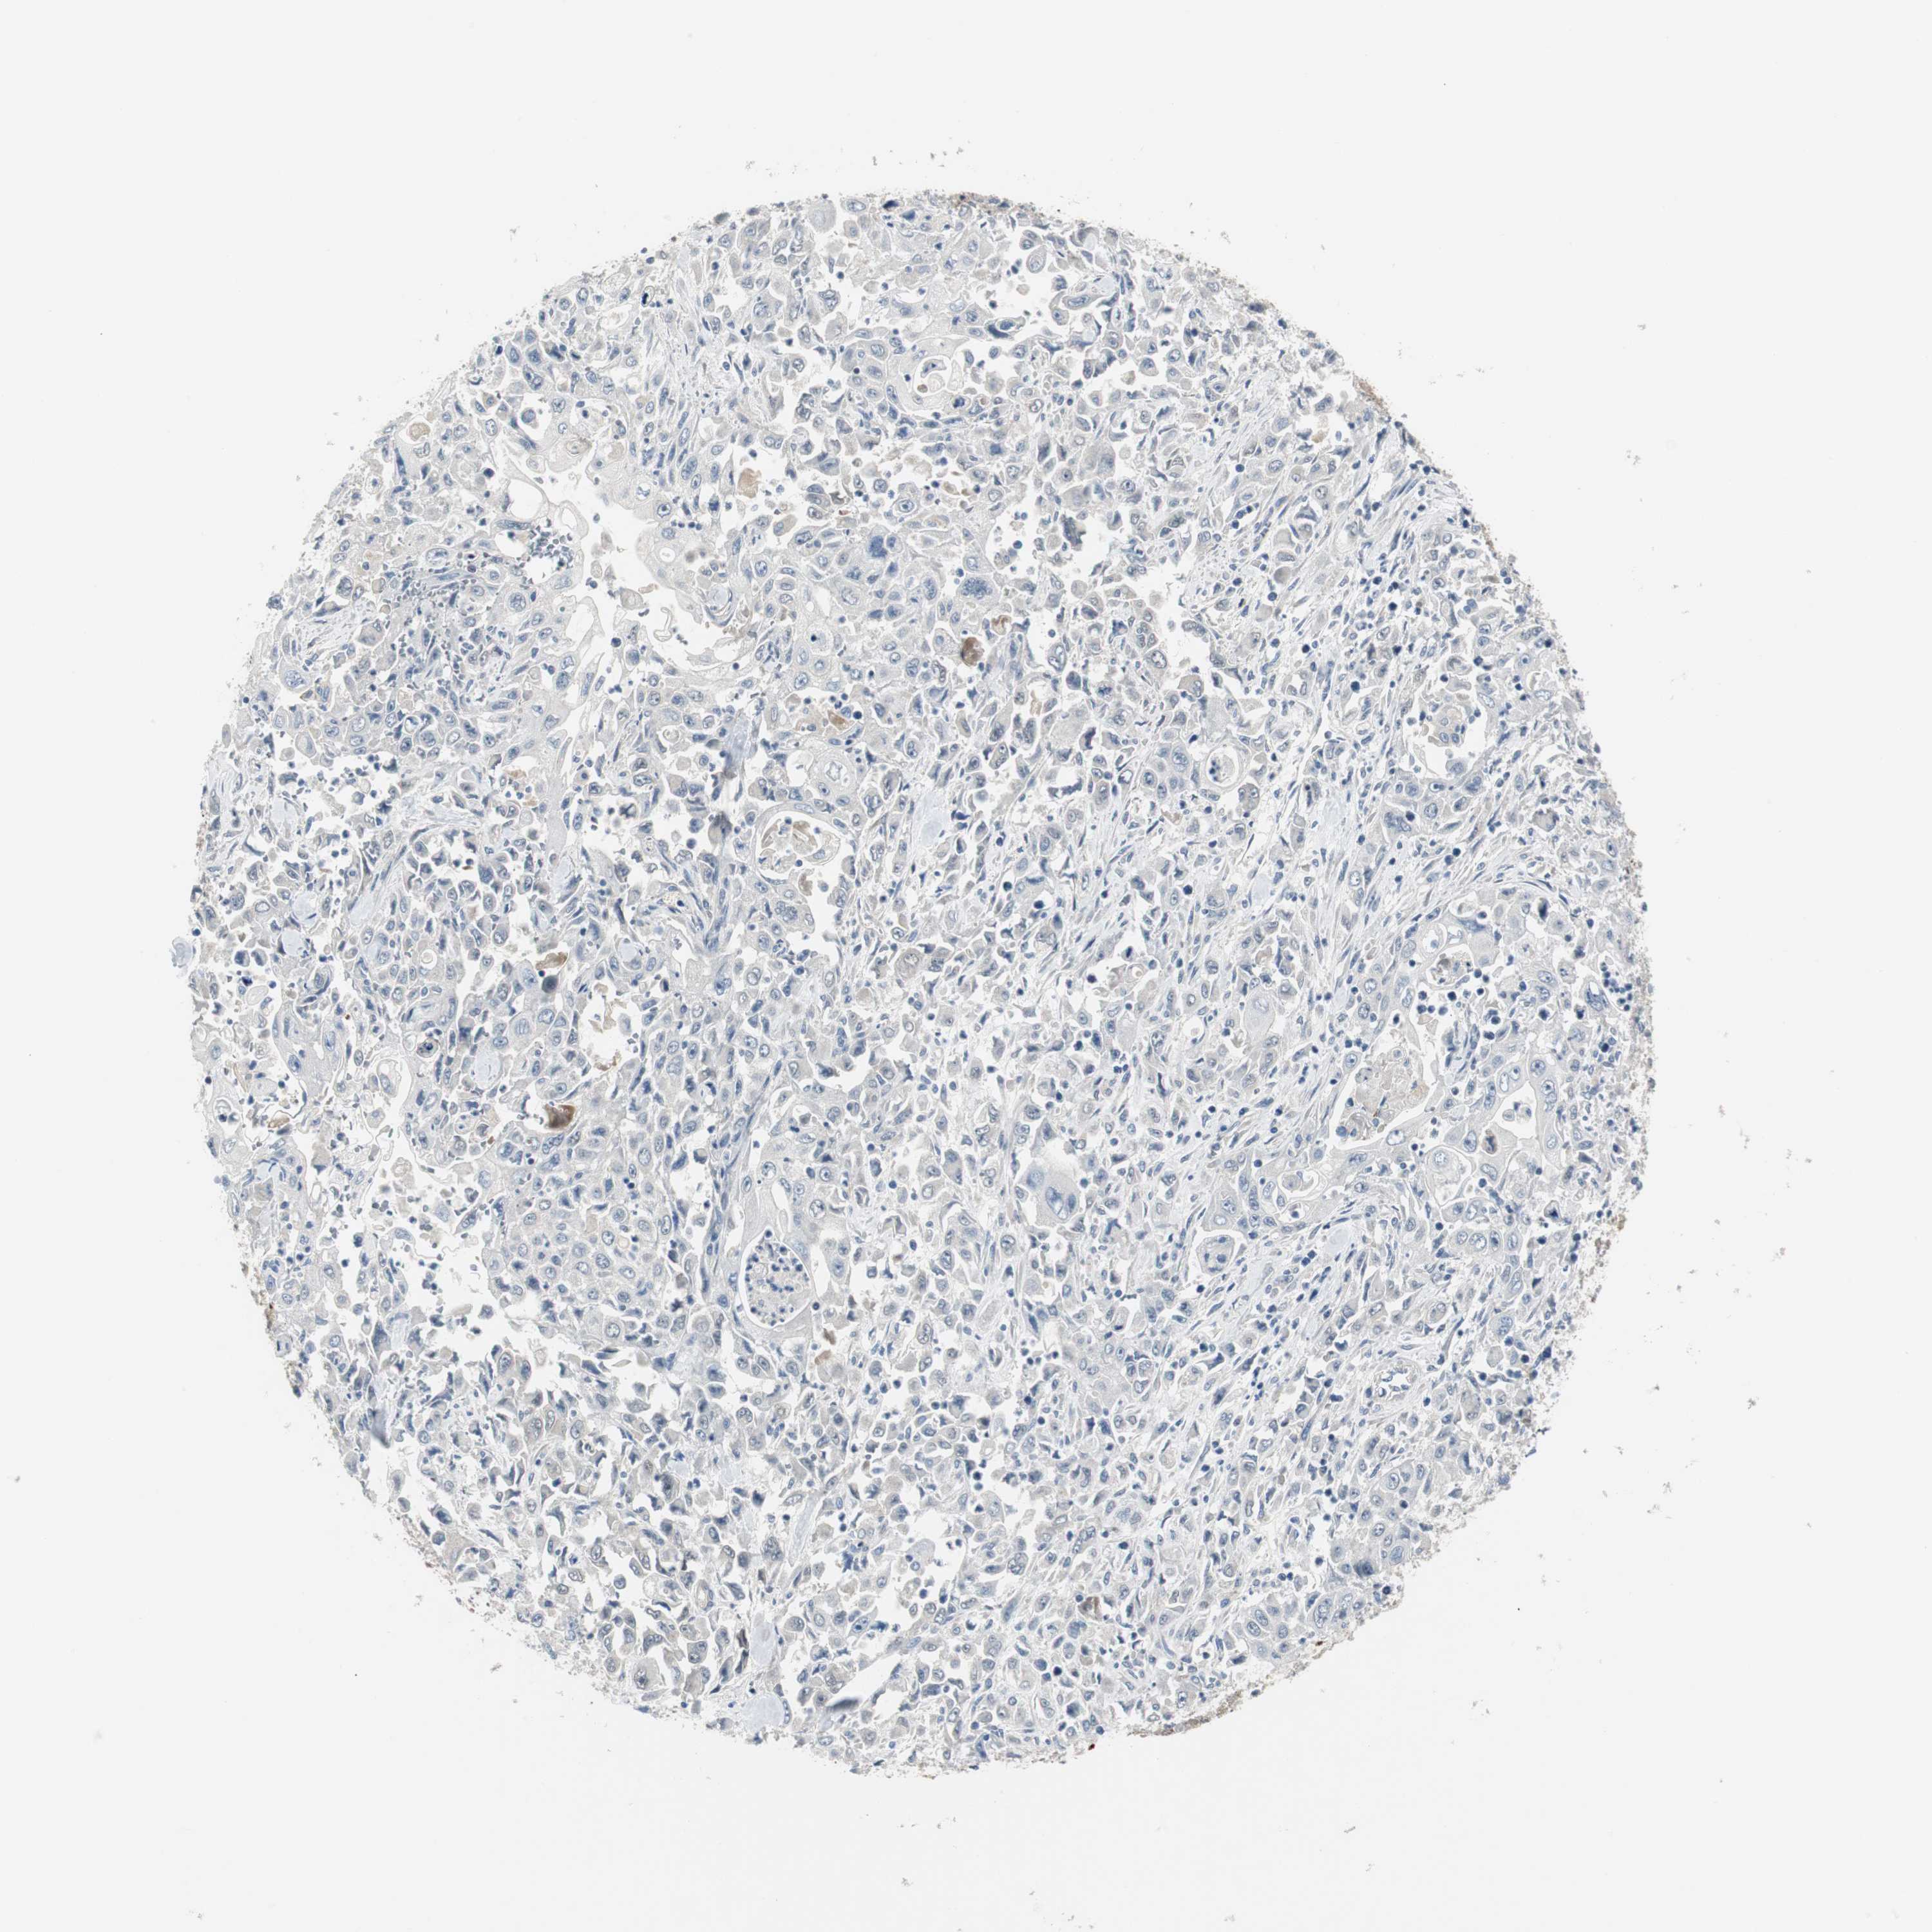

PANCREATIC CANCER - Protein expressioni

A mouse-over function shows sample information and annotation data. Click on an image to view it in a full screen mode. Samples can be filtered based on level of antibody staining by selecting one or several of the following categories: high, medium, low and not detected. The assay and annotation is described here.

Note that samples used for immunohistochemistry by the Human Protein Atlas do not correspond to samples in the TCGA dataset.

Antibody stainingi

Antibody staining in the annotated cell types in the current human tissue is reported as not detected, low, medium, or high, based on conventional immunohistochemistry profiling in selected tissues. This score is based on the combination of the staining intensity and fraction of stained cells.

Each image is clickable and will lead to virtual microscopy that enables deeper exploration of all samples and also displays staining intensity scores, fraction scores and subcellular localization as well as patient and tissue information for each sample.

Antibody HPA005922

Antibody HPA006028

Antibody CAB008368

Staining

High

Medium

Low

Not detected

Intensity

Strong

Moderate

Weak

Negative

Quantity

>75%

75%-25%

<25%

None

Location

Nuclear

Cytoplasmic/membranous

Cytoplasmic/membranous,nuclear

Adenocarcinoma, NOS

Adenocarcinoma, metastatic, NOS